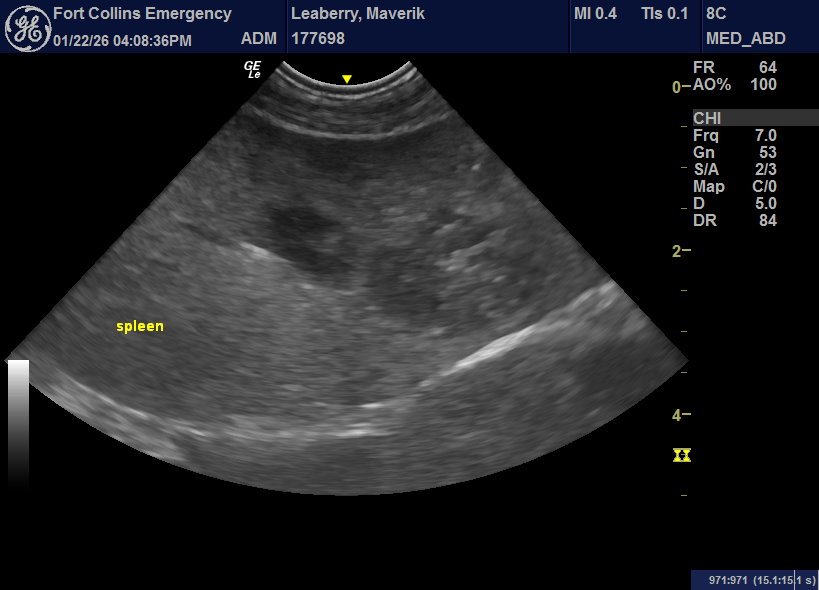

6 yr MI Lab diagnosed with a regenerative anemia with spherocytes, negative slide agglutination, no hematuria, T bili WNL. Spleen very enlarged and irregular and I could not connect the more dorsal structure to any organs. Did FNA’s on both the spleen and suspected mass. Both came back as extramedullary hematopoeisis. Looked so irregular to me, but was I wrong to aspirate? Is this what I should expect from a severely regenerative case? Any thoughts on the accessory splenic tissue?

With these signs IMHA is still possible – considering running a Coombs’ test. Screening for vector-borne diseases also recommended.

No issue with aspirating the spleen – although FNA came back as EMH, neoplasia is still possible and may need additional FNA.